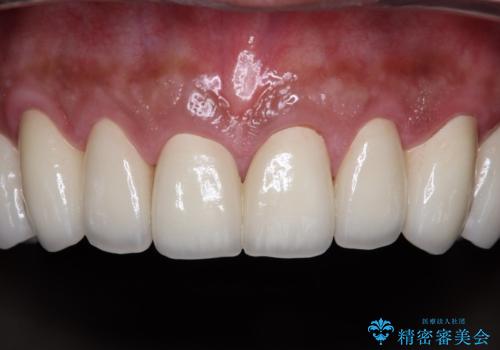

黄ばんだ前歯をきれいに 前歯の審美歯科治療

奥歯の銀歯も気にはなるものの、口を開けたときに目立たないとのことで、上下ともに前歯を中心にオールセラミッククラウンにて補綴治療を行うこととしました。

咬合力が非常に強いため、就寝時には上下ともにマウスピースを使用していただくよう指導をしています。